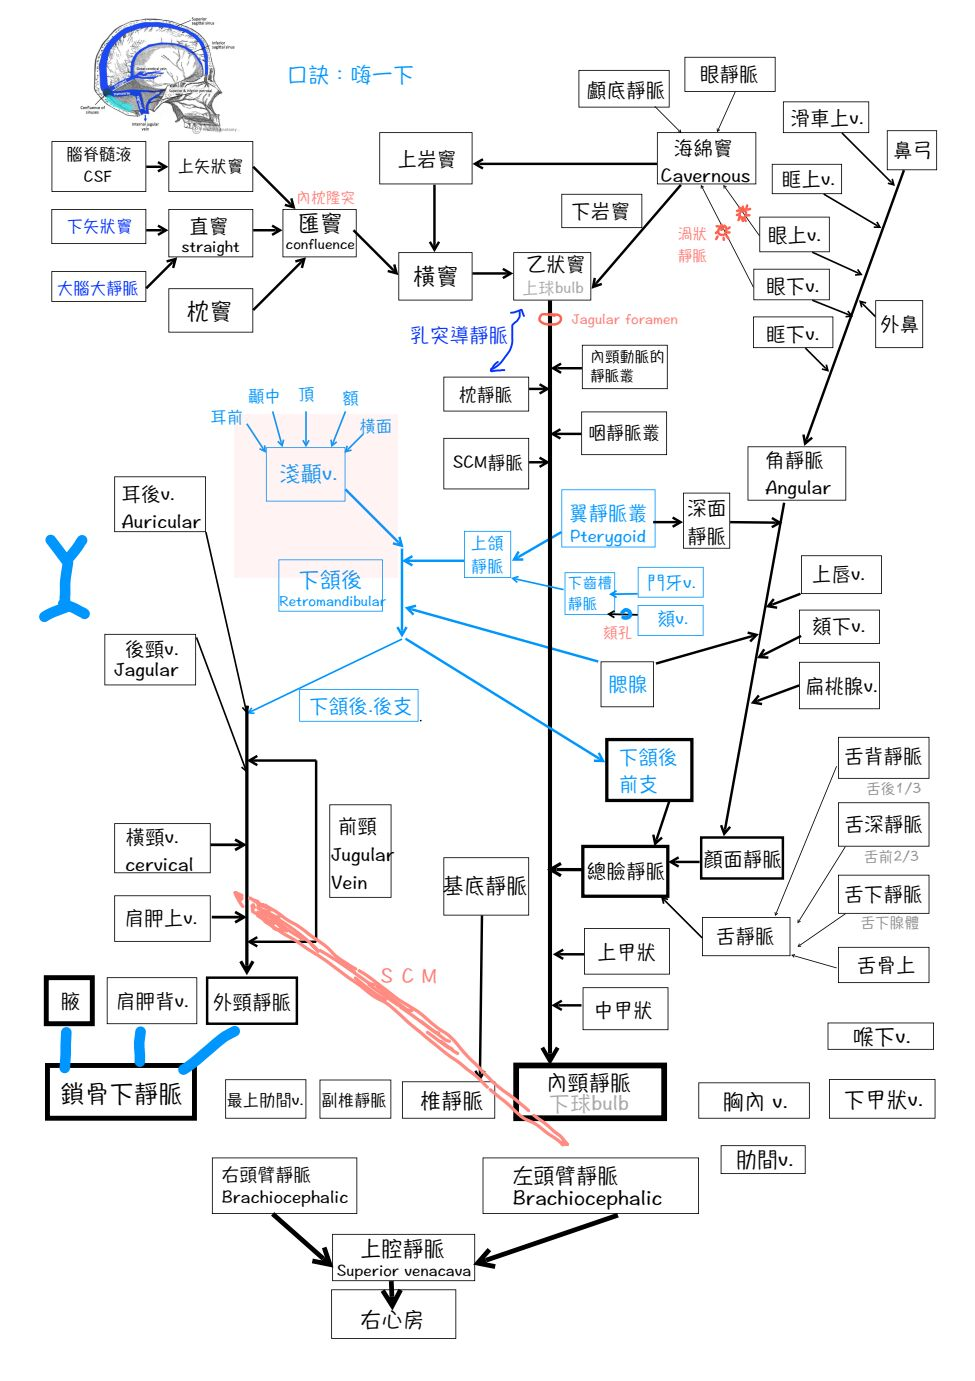

Vein

Info

subclavian vein 在ant. scalene m. 上方

顱內